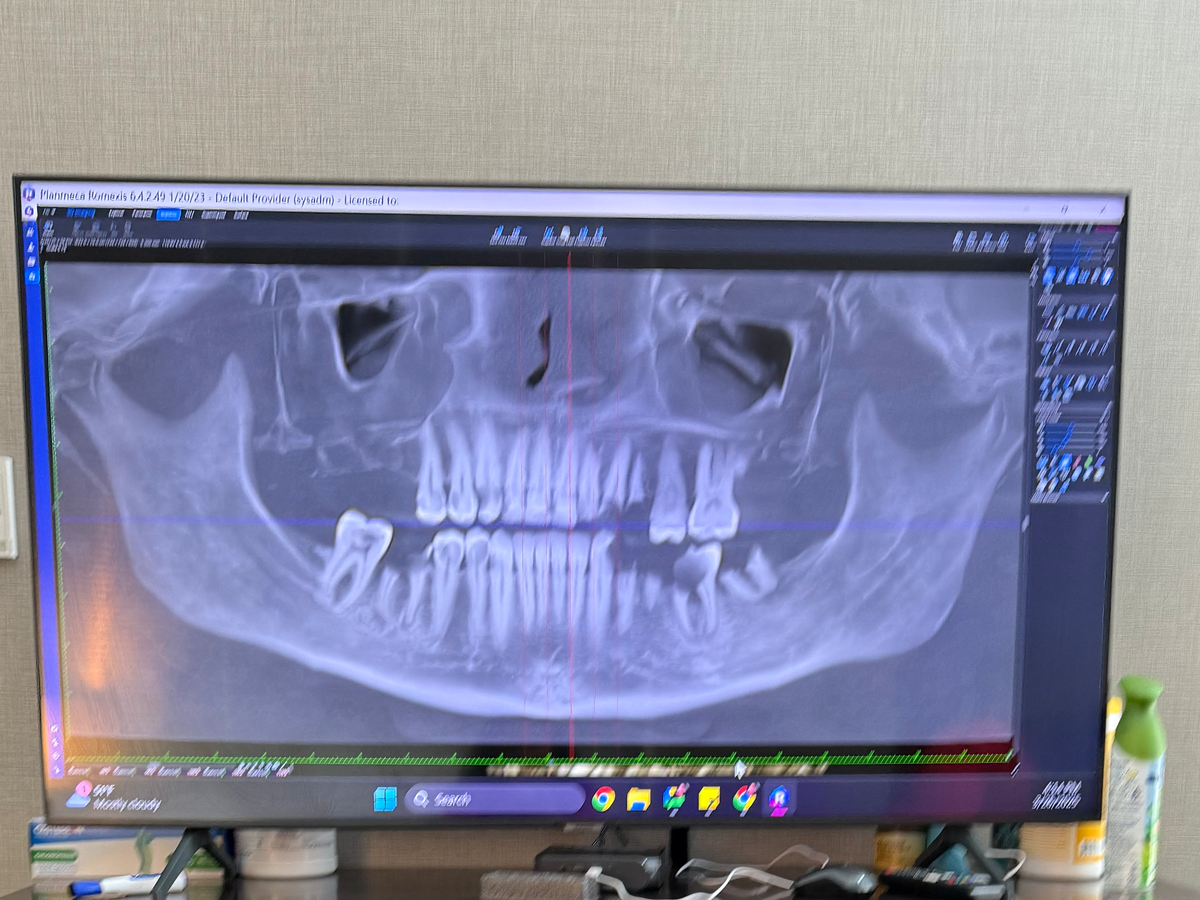

The photo X-ray that you’re looking above is the remnants of a once healthy smile and teeth. I’ve seen multiple oral surgeons, dentists, students, community health clinics—you name it, I’ve tried it. It can only be speculated that possibly this was caused by my birth control DEPO shot I had received for over a year in combination with severe reflux and Hyperemesis Gravidarum. My teeth were frequently exposed to stomach acid and vomit, leading to tooth decay. We again can only speculate, but the medication I took during my recovery has also been linked to severe tooth decay, and there are several class action lawsuits in process that I’ve applied for. Unfortunately, the statute of limitations on these are years long, and these cases sometimes never see any resolution. Before these events took place, I had a beautiful smile. I took great care of my teeth; I’d only had one cavity in my entire life, so this was a huge shock. I did everything in my power to find a dentist that took my insurance, but as more time went by, I had a couple of teeth pulled—whatever I could afford at the time or wherever they could squeeze me in. I was placed on urgent/emergency waitlists. Even pregnant with my son, I still couldn’t be seen for anything other than an emergency exam and some antibiotics, which were only a bandaid for what was inevitable.

Aside from the scary news I received, I was given a shred of hope at this appointment, as you will see in the photo I shared. After the X-rays and consultation, I was shown what I would look like with a healthy smile again. I have completely forgotten what it is like to smile or to even be able to eat dinner or go a day without sore, bleeding gums or taking a handful of ibuprofen just to go to sleep at night. I was a bit discouraged when I was told the price of the screw-in veneers. The prosthodontist suggested an overdenture, which was $10,000, or screw-in veneers, as I am young and have good bone structure, and she didn’t want my face to change shape over time. I knew I didn’t have $10,000 for an overdenture and certainly didn’t have $50,000 for screw-in veneers. The only other option was a top and bottom denture. I have posted a photo of my appointment prognosis and the price. I would never even attempt to raise $50,000, but after feeling completely defeated and applying and being denied for all third-party lenders, I had to make a last-ditch effort and put myself out there completely vulnerable in a desperate attempt to save my teeth and my health. The last thing I want to do is ask complete strangers or even friends and family to help with this, but I’m all out of options. I truly wish I could have kept all this to myself and just kept hiding it, but it’s reached the point where something awful could happen, and the thought of not being there to watch my kids grow up is terrifying.